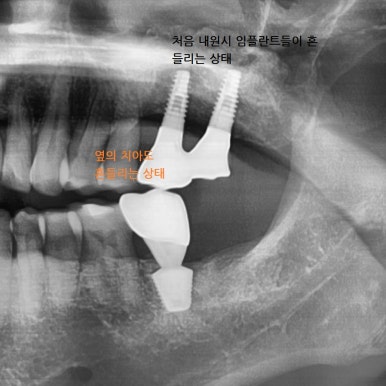

흔들리는 옆 치아와 흔들리는 임플란트를 제거하고 임플란트2개와 임플란트 브릿지로 마무리

흔들리는 옆 치아1개와 흔들리는 임플란트2개를 제거하고

3개의 자리를 임플란트2개와 가짜머리1개가 있는 임플란트 브릿지로

3개의 자리를 마무리하였습니다.

1.흔들리던 임플란트 2. 임플란트 제거 후 3.임플란트 재수술 후